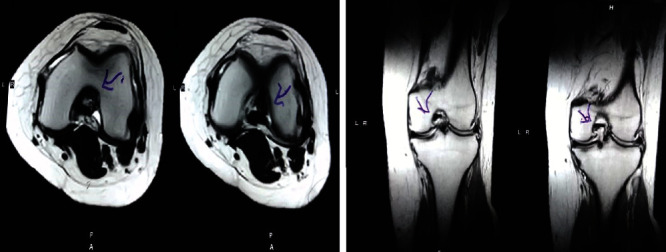

治療后一個(gè)月進(jìn)行隨訪。在第一次細(xì)胞治療后,患者的疼痛明顯減輕。第二次療程后,她沒(méi)有疼痛,并注意到運(yùn)動(dòng)范圍有所改善。持續(xù)的物理治療也觀察到下肢肌肉力量的增加。從治療開(kāi)始(11個(gè)月前)到最后一次隨訪(4個(gè)月前),患者按照建議的飲食和基于運(yùn)動(dòng)的方案減重了11公斤。因此,她現(xiàn)在整體身體健康,能夠更舒適地進(jìn)行日常生活活動(dòng)。表3顯示治療前后的MRI檢查結(jié)果。人物的圖1和的和圖2顯示半月板撕裂的治療前和治療后(1年后)圖片。觀察到損傷程度的改善圖2。